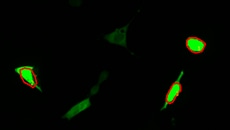

钙成像的观察事例

如果引进一体化荧光显微成像系统BZ-X

- 无需暗室、操作简单,可非常清晰地进行显微镜观察。

- 利用由制冷相机和专用镜头构成的高灵敏度光学系统,能够在尽量减少细胞损伤的同时,获取高精细的荧光图像。

- 能够一次性对多个标本进行延时拍摄,便于开展相同条件下的比较检验。